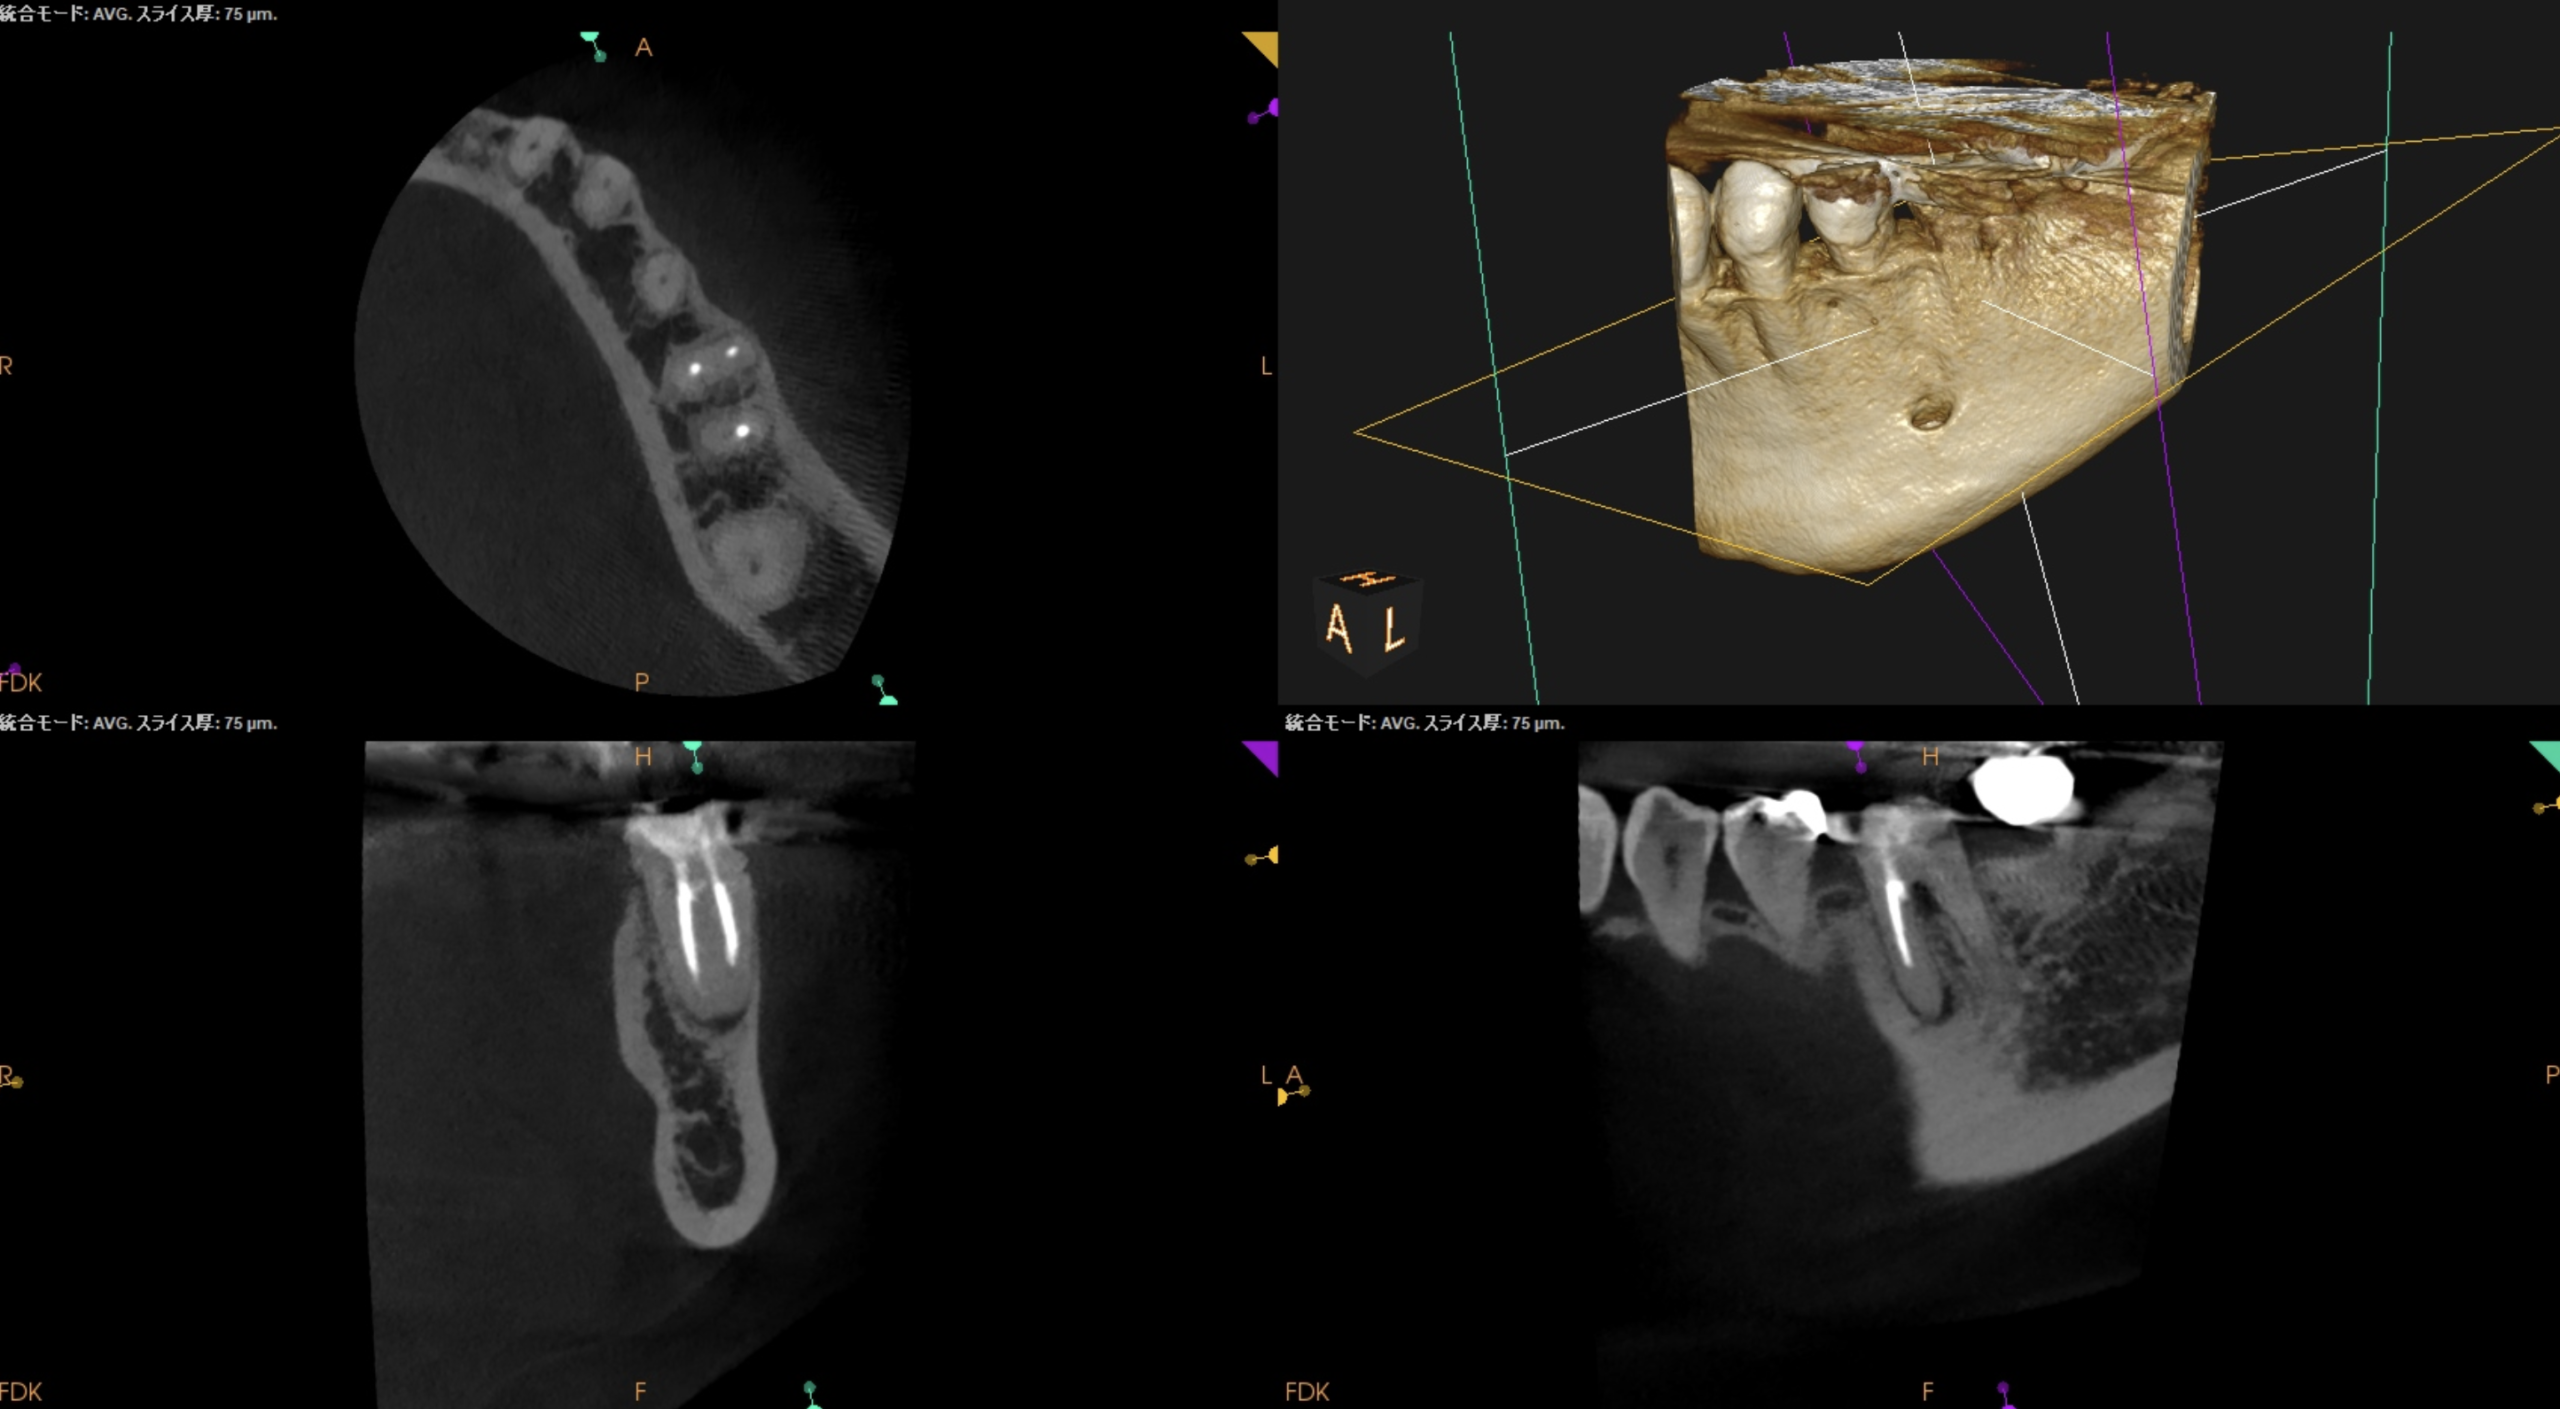

CBCTも撮影した。

CBCT(2025.10.31)

#19

MB

ML

D

ということで臨在歯の#18もCBCTを精査した。

#18

M

#18 Mのこの絵は縁下カリエスの可能性を示唆している。